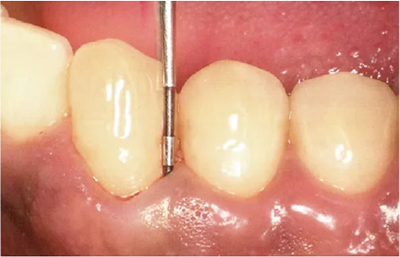

探針在牙周袋內(nèi)的工作方式

~步行式探診~

牙周探診在掌握眼睛看不到的部分的狀態(tài)方面,是非常重要的一個檢查。參考X片進(jìn)行探診,可以立體掌握該檢查部位。

然而X片中無法看到所有信息。魚食,牙周探針的工作尖需要像步行一樣在袋底走動運用步行式探診法可以更準(zhǔn)確掌握該部位的狀況。

此時運用的牙周探診技巧稱為“步行式牙周探診法”。

● 步行式牙周探診的操作

牙周探針的工作尖始終與牙體接觸,將工作尖從袋底上提1~2mm的幅度進(jìn)行步行式探診。